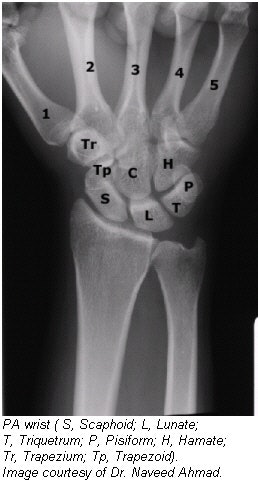

Radiographic positioning of the wrist

The routine radiographic examination of the wrist uses the frontal and lateral projections. The PA radiograph is best obtained with the arm abducted 90° from the trunk and the forearm flexed at 90° to the arm. For the evaluation of arthritis, oblique projections also are necessary. These latter projections should include radiographs exposed with the wrist in both a semipronated oblique and a semisupinated oblique position.

Positioning for PA wrist projection

- Have the patient rest their forearm on the table, and center the wrist to the cassette area.

- Seat the patient low enough to place the axilla in contact with the table, or elevate the limb to shoulder level on a suitable support.

- Adjust the hand and forearm to lie parallel with the long axis of the cassette.

- Slightly arch the hand at the MCP joints by flexing the digits to place the wrist in close contact with the cassette.

- CR: Perpendicular to the midcarpal area

![]() |

Evaluation criteria for AP and PA wrist

- The carpal interspaces are better demonstrated in the AP image than the PA interspaces; they are more closely parallel with the divergence of the x-ray beam.

- Long axis of the hand, wrist, and forearm is aligned with IR.

- True PA is evidenced by the following: Equal concavity shapes are on each side of the shafts of the proximal metacarpals; near equal distances exist among the proximal metacarpals; separation of the distal radius and ulna is present, except for possible minimal superimposition at the distal radioulnar joint.

- Soft tissue and bony trabeculation should be visible.